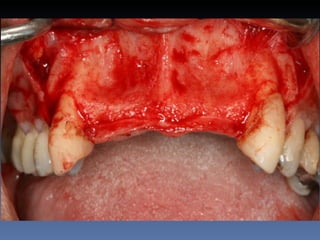

BOX 2

Sebastião Moreira Souza

Idade – 49 anos

Sexo – Masculino

Raça – Caucasiana

ASA – II

Data- 23-04-2012

Diagnóstico: Desdentado total maxila

Plano de tratamento:          Reabilitação com 6 blocos

“onlay” e “sinus-llift” bilateral, provenientes de Úmero

fresco-congelado (FFB); reabertura para instalação

de 6 implantes dentários endo-ósseos e reabilitação

protética fixa.